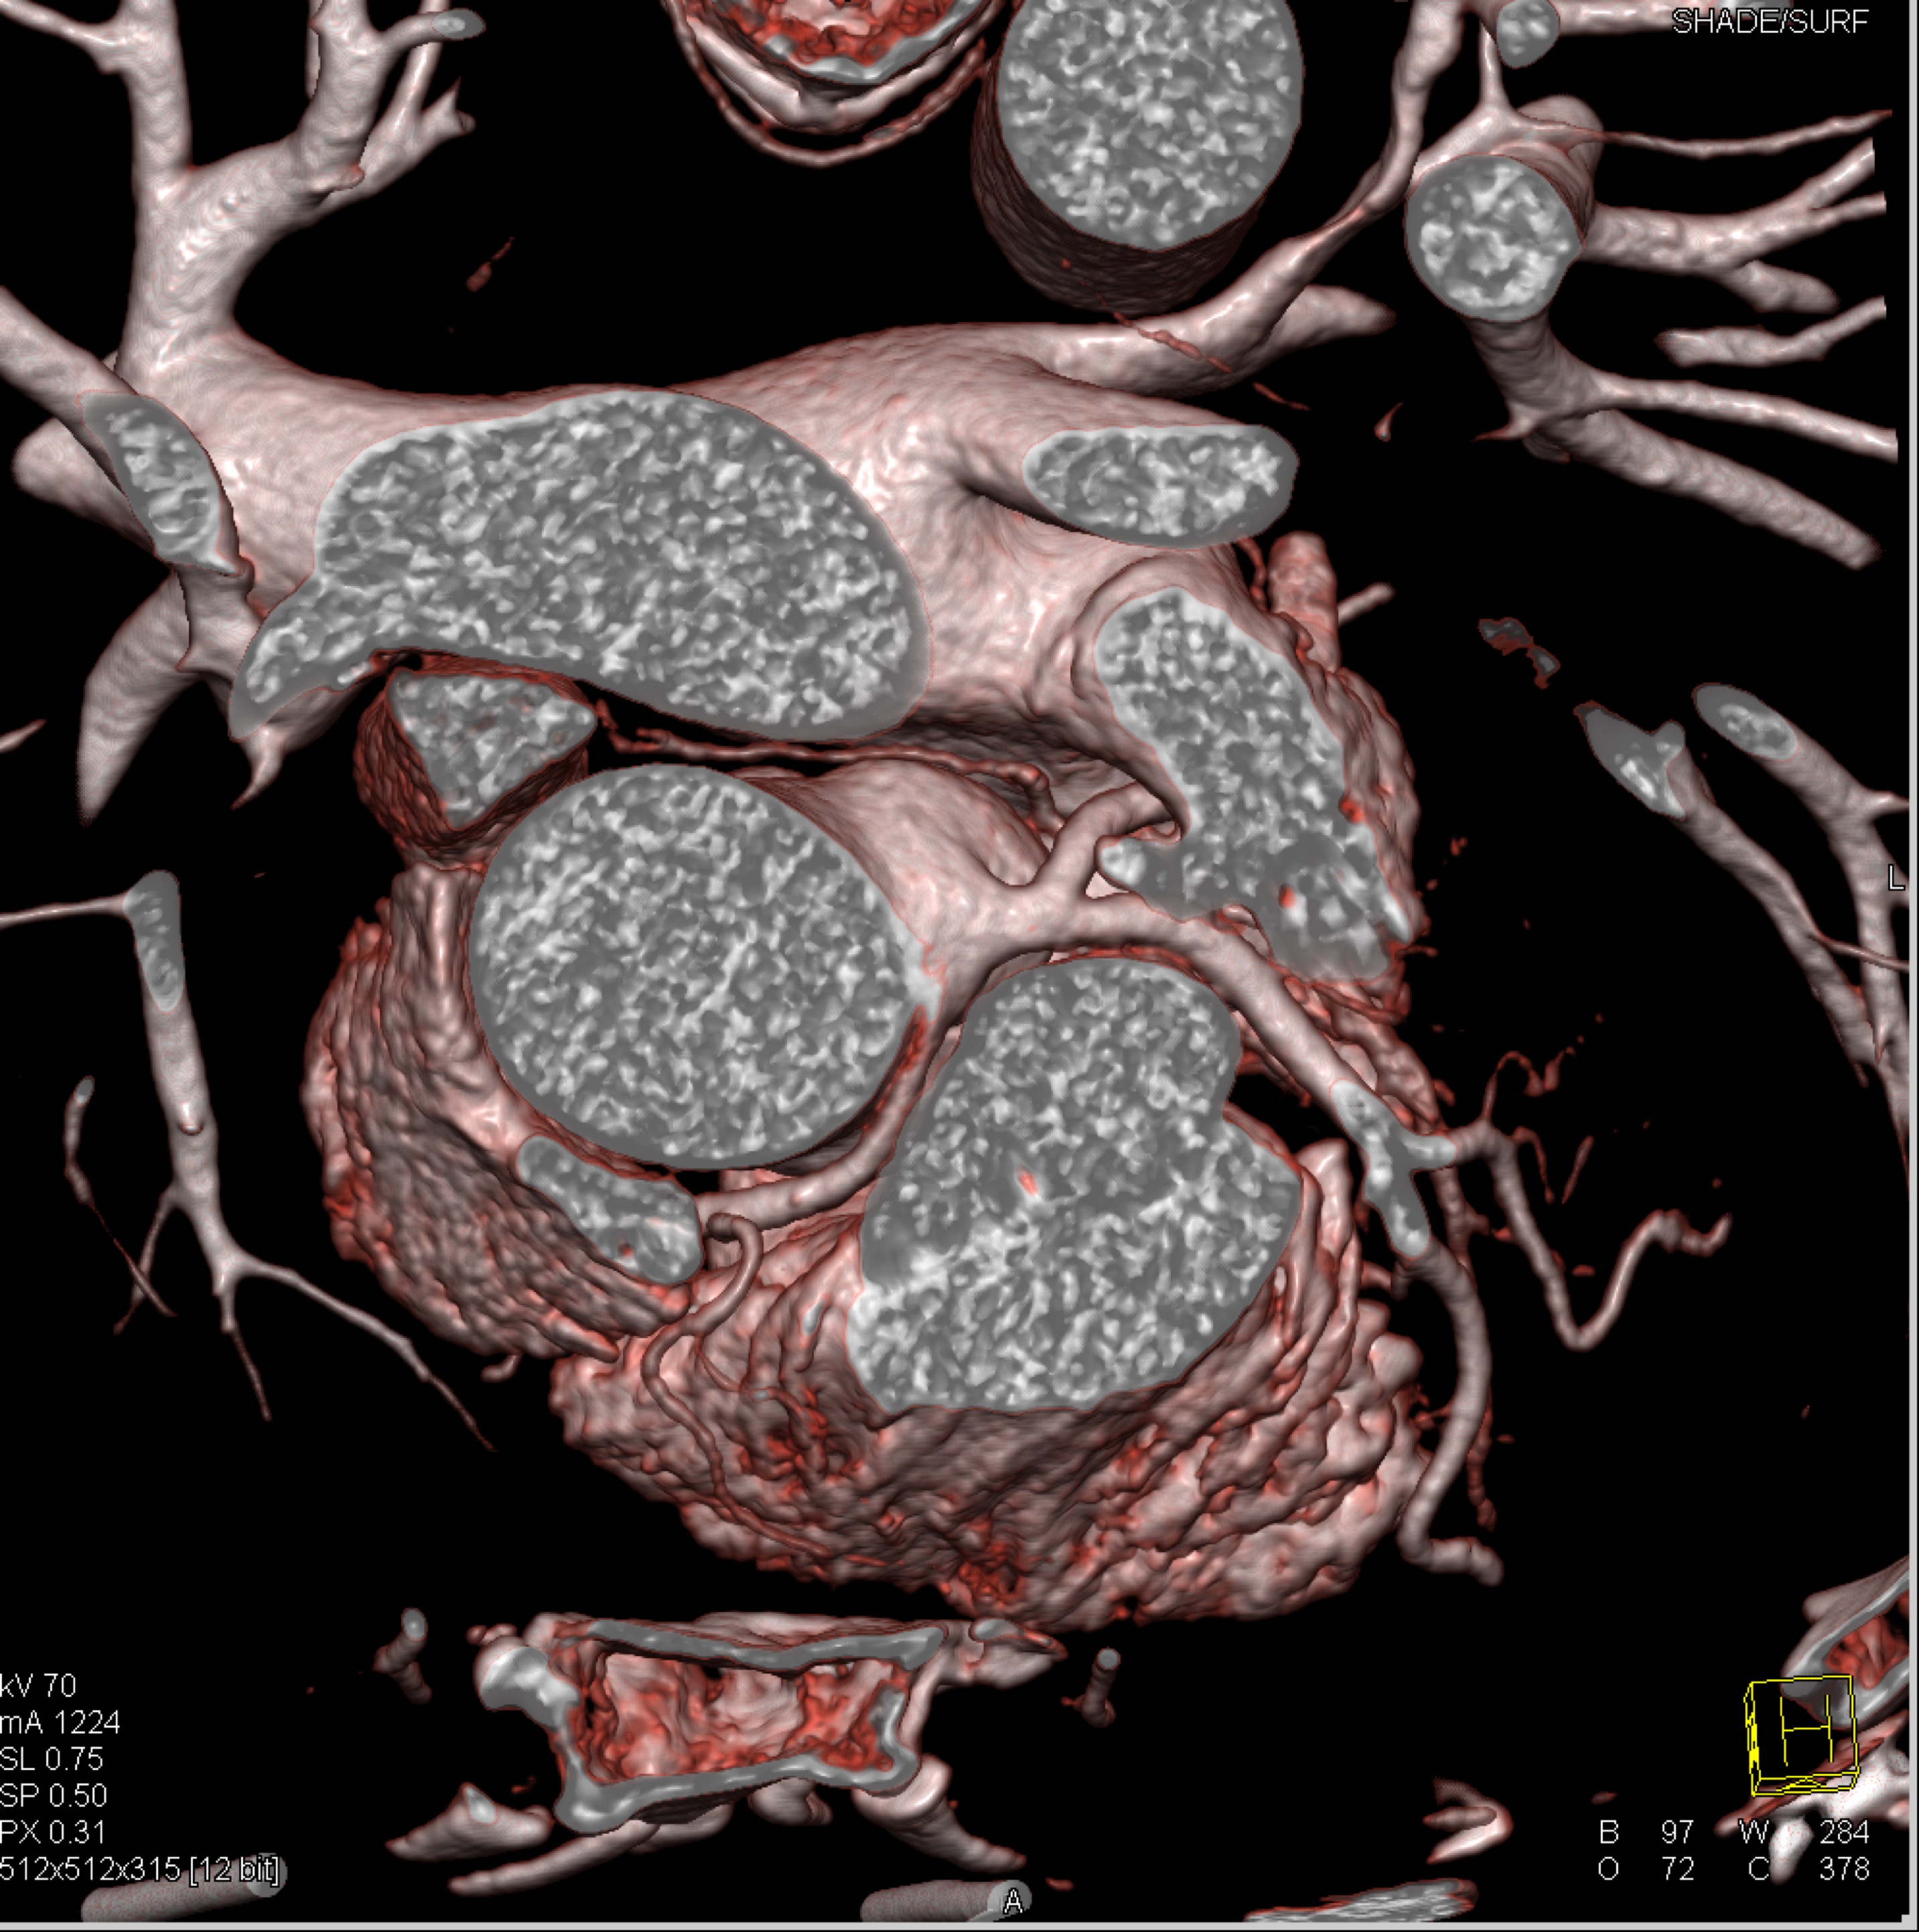

- Select the best answer

- Submit your answers by selecting the "Submit" button at the end of the quiz.

6) The most likely diagnosis in this case is?

vegetations in pulmonary valve

failed pulmonic valve

normal appearance of repaired pulmonary valve

abscess of the pulmonary artery